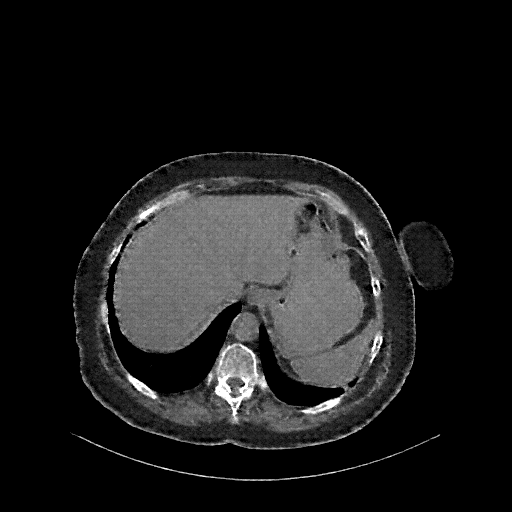

Original NATIVE CT scan (input)

Full window (WL 1023.5, WW 4095 β†’ Low βˆ’1024, High +3071)

Reconstructed NATIVE CT scan (cycle consistency)

Original VENOUS CT scan

Generated VENOUS CT scan (A→B translation)